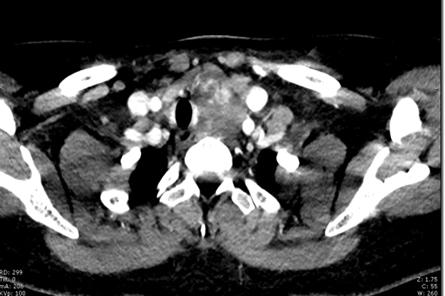

通过完善颈部增强CT、肺CT、纤维喉镜等相关检查,结果显示患者甲状腺左侧叶的巨大肿瘤已经挤压得气管严重右偏,部分腺体已经生长到了胸骨后,而且甲状腺的最下端已经深入到主动脉弓的位置。